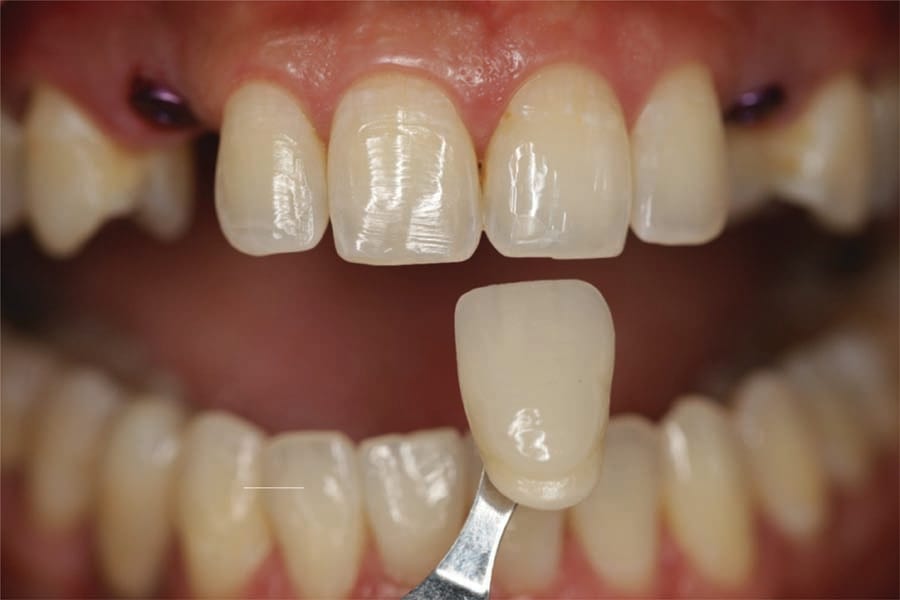

At 2 weeks post implant uncovery the patient returned. The healing abutments were removed and scan bodies placed. Intraoral scanning was performed (Primescan) to fabricate a custom abutment and provisional crowns (Figure 16). The healing abutments were reinserted. Shade A1 was selected to match the adjacent dentition (Figure 17) and the patient dismissed.